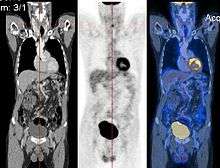

Image registration is a process that searches for the correct alignment of images.[9][10][11][12] In the simplest case, two images are aligned. Typically, one image is treated as the target image and the other is treated as a source image; the source image is transformed to match the target image. The optimization procedure updates the transformation of the source image based on a similarity value that evaluates the current quality of the alignment. This iterative procedure is repeated until a (local) optimum is found. An example is the registration of CT and PET images to combine structural and metabolic information (see figure).

- Combining complementary information from different imaging modalities. An example is the fusion of anatomical and functional information. Since the size and shape of structures vary across modalities, it is more challenging to evaluate the alignment quality. This has led to the use of similarity measures such as mutual information.[13]